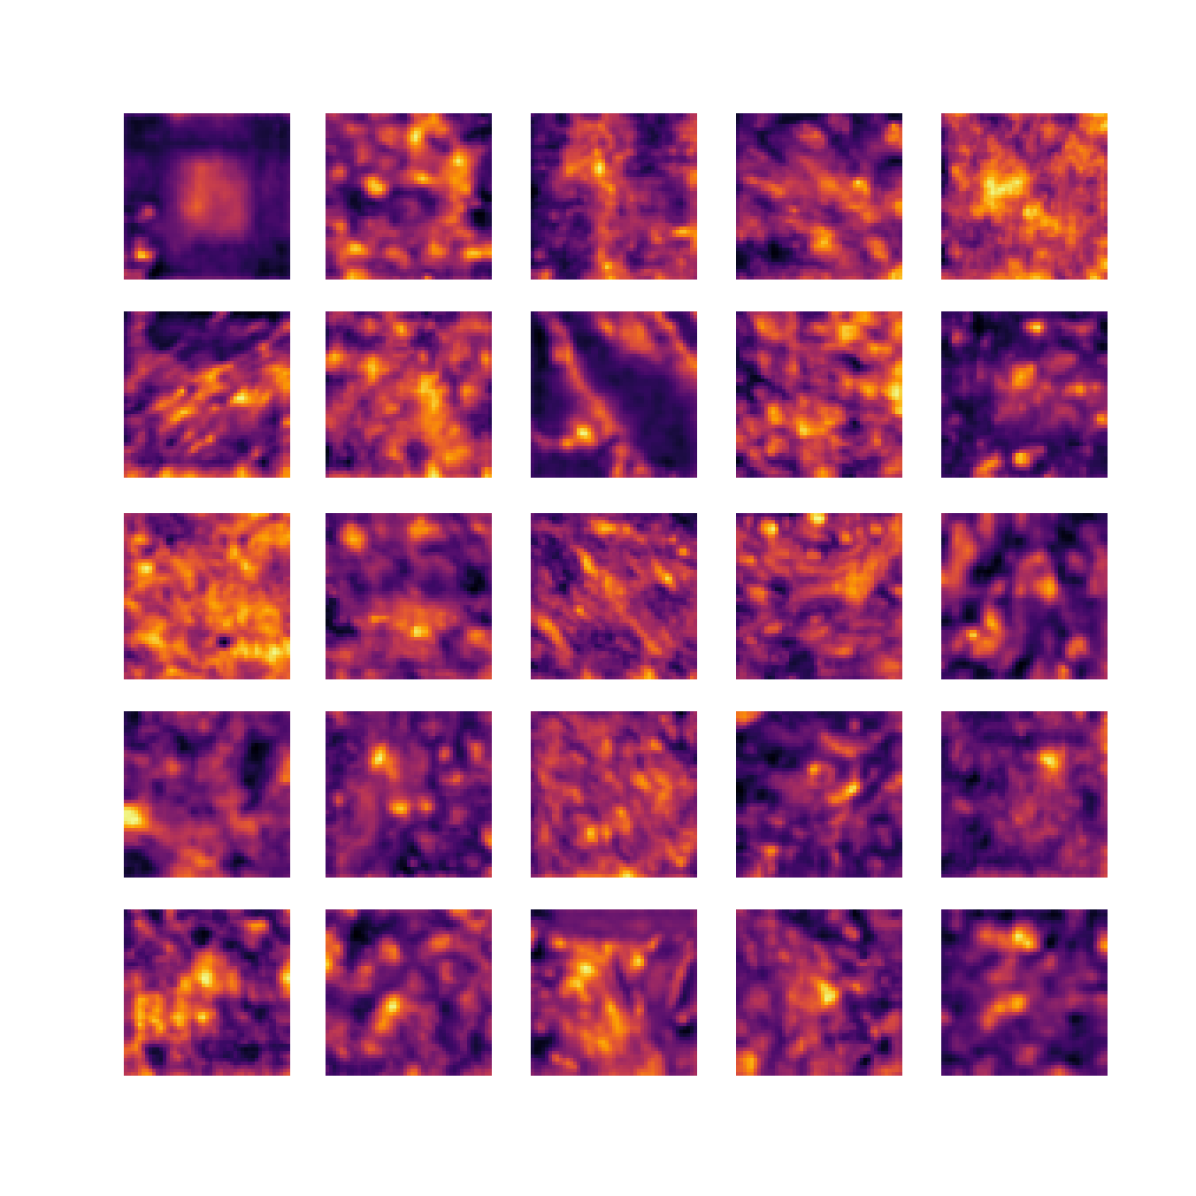

We also analyse the activation maps for each model using GradCAM as described in section S3. This offers more insight into the areas of the image which are contributing most heavily to the models’ representations. In Figure 4(b) we present some representative examples, however, a larger selection which was chosen at random is presented in Figures S10 to S25. The larger selection makes it easier to see the emergent patterns, including that privileged Siamese models tend to mainly identify features which are strongly present in both inputs, while unprivileged Siamese models tend to learn more diffuse features that are not specific to one cell phenotype or image region. TriDeNT ♆ incorporates both sets of features, learning both features specific to the privileged data and more the general features associated with unprivileged Siamese networks.

We can see in Figure 4(b) panel A that for ERG, the privileged Siamese model focuses almost exclusively on any nuclei which could be endothelial cells. As there are very few endothelial cells in the dataset, it could be an effective strategy to identify anything that could potentially be an endothelial cell to minimise the difference between the representations of the H&E model and the IF mask model. In the corresponding unprivileged Siamese image, we see that the model identifies some of these nuclei, albeit less strongly, but also focuses heavily on the other tissue and even the background, while strongly fixating on two spots of debris in the center of the image. This model has less ‘incentive’ to learn the weak features related to endothelial cells as these occur rarely and are not easy to detect, while more generic strong features such as the presence of connective tissue and the prevalence of background are more common and predictable from augmented images. We see that TriDeNT ♆ combines these two feature sets, strongly identifying nuclei while also identifying the connective tissue.

In panel C we see a similar pattern, with the privileged Siamese model fixating solely on the nuclei, while the TriDeNT ♆ model takes a more balanced approach. The unprivileged Siamese model appears to focus on a single cluster of nuclei while neglecting others, and similarly identifies an area of fibroblasts with its distinctive pattern but does not others.

In contrast to panels A and C which represent models with poor privileged Siamese results, panels B and D represent models whose privileged Siamese results were comparable to both TriDeNT ♆ and even the supervised baseline. It is therefore interesting to note that there are far more similarities between the privileged Siamese and TriDeNT ♆ models in both cases. Particularly in panel B, TriDeNT ♆ and the privileged Siamese model return virtually identical heatmaps, with both strongly identifying epithelial nuclei and neglecting the same areas of connective tissue. The unprivileged model in this case appears to focus solely on the centre of the image, giving a significantly different heatmap to the other panels.

Panel D again shows the previous pattern, with the privileged Siamese model identifying the features strongly present in the privileged data – fibroblasts – while neglecting the nuclei present. TriDeNT ♆ also strongly identifies the connective tissue, but, unlike the privileged Siamese model, does not completely neglect the nuclei. The unprivileged Siamese model primarily identifies background, and does not appear to identify the nuclei in this example.